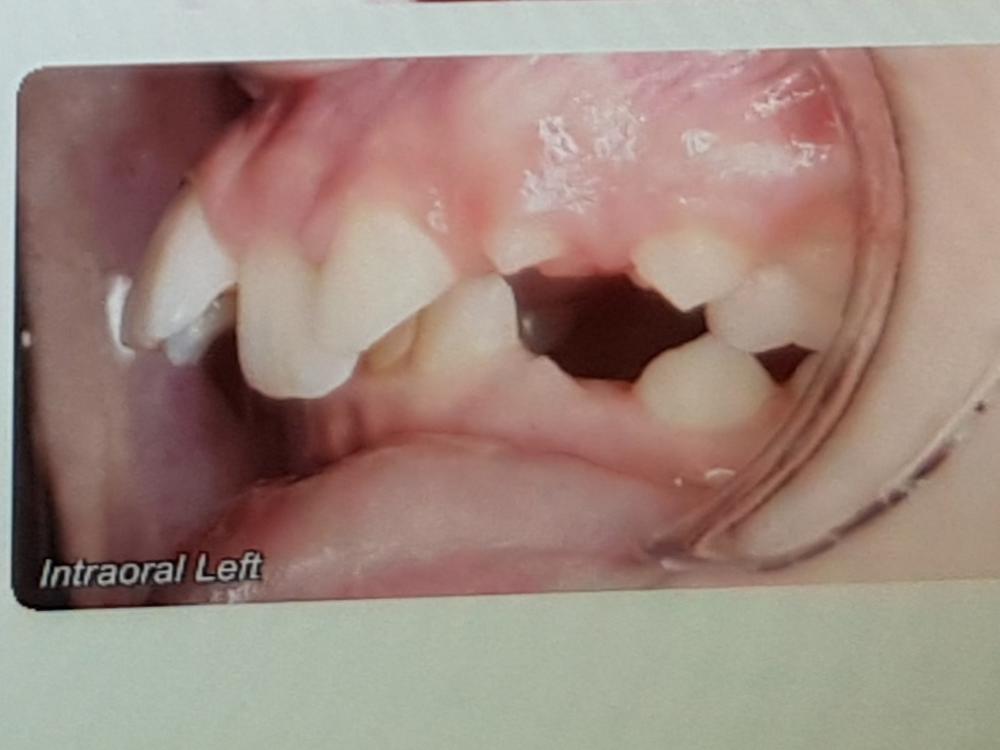

My son's teeth

My son needs work on his jaw and teeth. He is 12 and has very low confidence, maybe a result of his teeth. His identical twin brother has straight teeth.

We have had a quote from an orthodontist and he will need Twin Blocks for several months to bring his bottom jaw forward (he has a severe overbite). At the same time, he will have 6 top braces to begin to straighten his teeth (he also has severe overjet).

After several months, he will then have a full set of braces. Total length of treatment is expected to be 24 months.